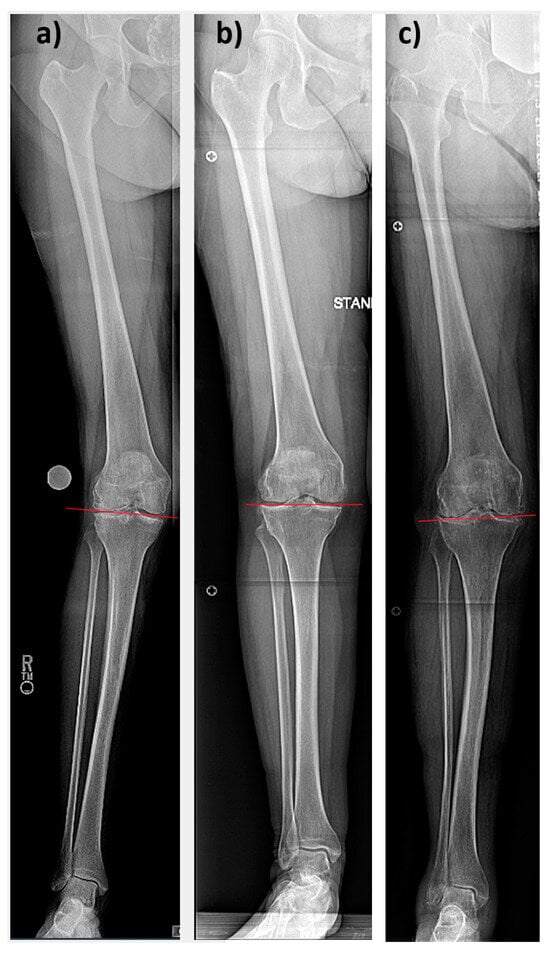

| Mean [°] | Range [°] | Standard Deviation [°] | |

| Preoperative | |||

| HKA | 187.4 | 181.6–197.7 | 3.9 |

| LDFA | 85.4 | 81.4–89.9 | 2.1 |

| MPTA | 90.4 | 84.6–98.0 | 2.6 |

| Postoperative | |||

| HKA | 179.6 | 172.8–187.3 | 2.5 |

| LDFA | 90.9 | 84.9–96.1 | 2.0 |

| MPTA | 90.4 | 86.8–93.1 | 1.4 |

| Changes pre- to postoperative | |||

| ΔHKA | 8.9 | −1.8- 31.3 | 5.9 |

| ΔLDFA | −5.8 | −20.7–−0.1 | 2.9 |

| ΔMPTA | 0.2 | −7.0–11.4 | 3.1 |